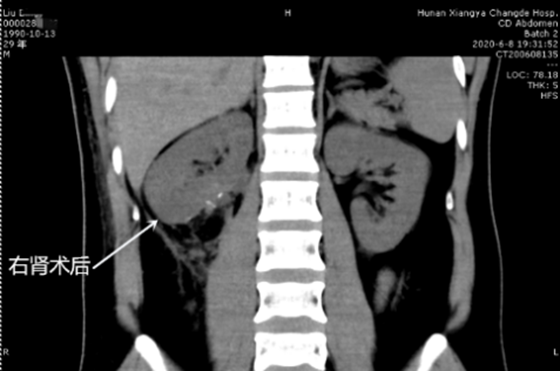

刘先生选择入院后,蒋欣杰副主任医师及其肿瘤性团队很快安排了增强CT等检查,并运用最近先进的3D打印技术,完全复原了肿瘤和血管等,术前围绕潜在风险进行充分讨论,并制定了周密的应急预案,麻醉科及输血科也随时准备,为手术定位保驾护航。接下来的手术中,蒋欣杰医师运用腹腔镜技术,“抽丝剥茧”般的细致耐心,完美切除右肾错构瘤,无周围副损伤,拆除“炸弹”的同时保护好了右肾;术后复查CT,右肾几乎恢复到正常。

术后

据蒋欣杰副主任医师介绍:该患者右肾错构瘤巨大,与肾动静脉及输尿管关系密切,稍有不慎就可能损伤。因此切除过程中,必须仔细游离、精准切除,做到极限保肾。目前,患者恢复良好并顺利出院,但要患者定期复查,预防肿瘤复发。